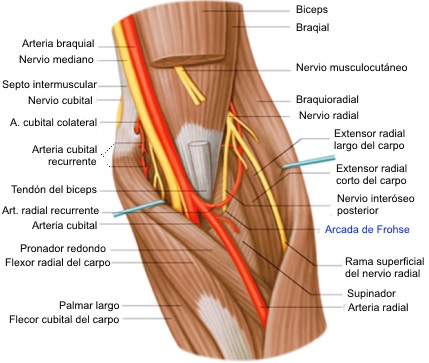

- El sitio más frecuente de compresión es en la

parte proximal del antebrazo en el área donde el músculo

supinador forma un arco fibroso por donde penetra la rama

interosea posterior (la llamada arcada de Fröhse).

Síndrome del túnel radial

profunda del nervio radial). Los sitios de compresión incluyen las

bandas fibrosas insertadas a la articulación radiocapitelar, vasos

recurrentes radiales, el origen tendinoso del extensor radial corto

del carpo, el origen tendinoso del supinador (es decir, arcada de

Frohse), y engrosamientos fibrosos dentro y en el margen distal del

supinador.

Síndrome del nervio interóseo

La etiología del síndrome del nervio

interóseo posterior es similar a la del síndrome del túnel radial.

La compresión se cree que se producen después de despegar las ramas

a los extensores radiales de la muñeca y el nervio sensitivo radial.

Después de salir del supinador, el nervio puede ser comprimido antes

de que se bifurca en ramas medialea y laterales, causando una

parálisis completa de los extensores digitales y desviación

dorsorradial de la muñeca secundaria a parálisis del extensor

cubital del carpo.

Si se produce la compresión después de que se bifurque el nervio, se

produce parálisis selectiva de los músculos, dependiendo de qué rama

se tratara. La compresión de la rama medial causa parálisis de los

extensor cubital del carpo, extensor del meñique, y extensor común

de los dedos. La compresión de la rama lateral causa parálisis del

abductor largo del pulgar, extensor corto del pulgar, extensor largo

del pulgar, extensor y propio del índice. Más comúnmente, el

atrapamiento se produce en el borde proximal del supinador.